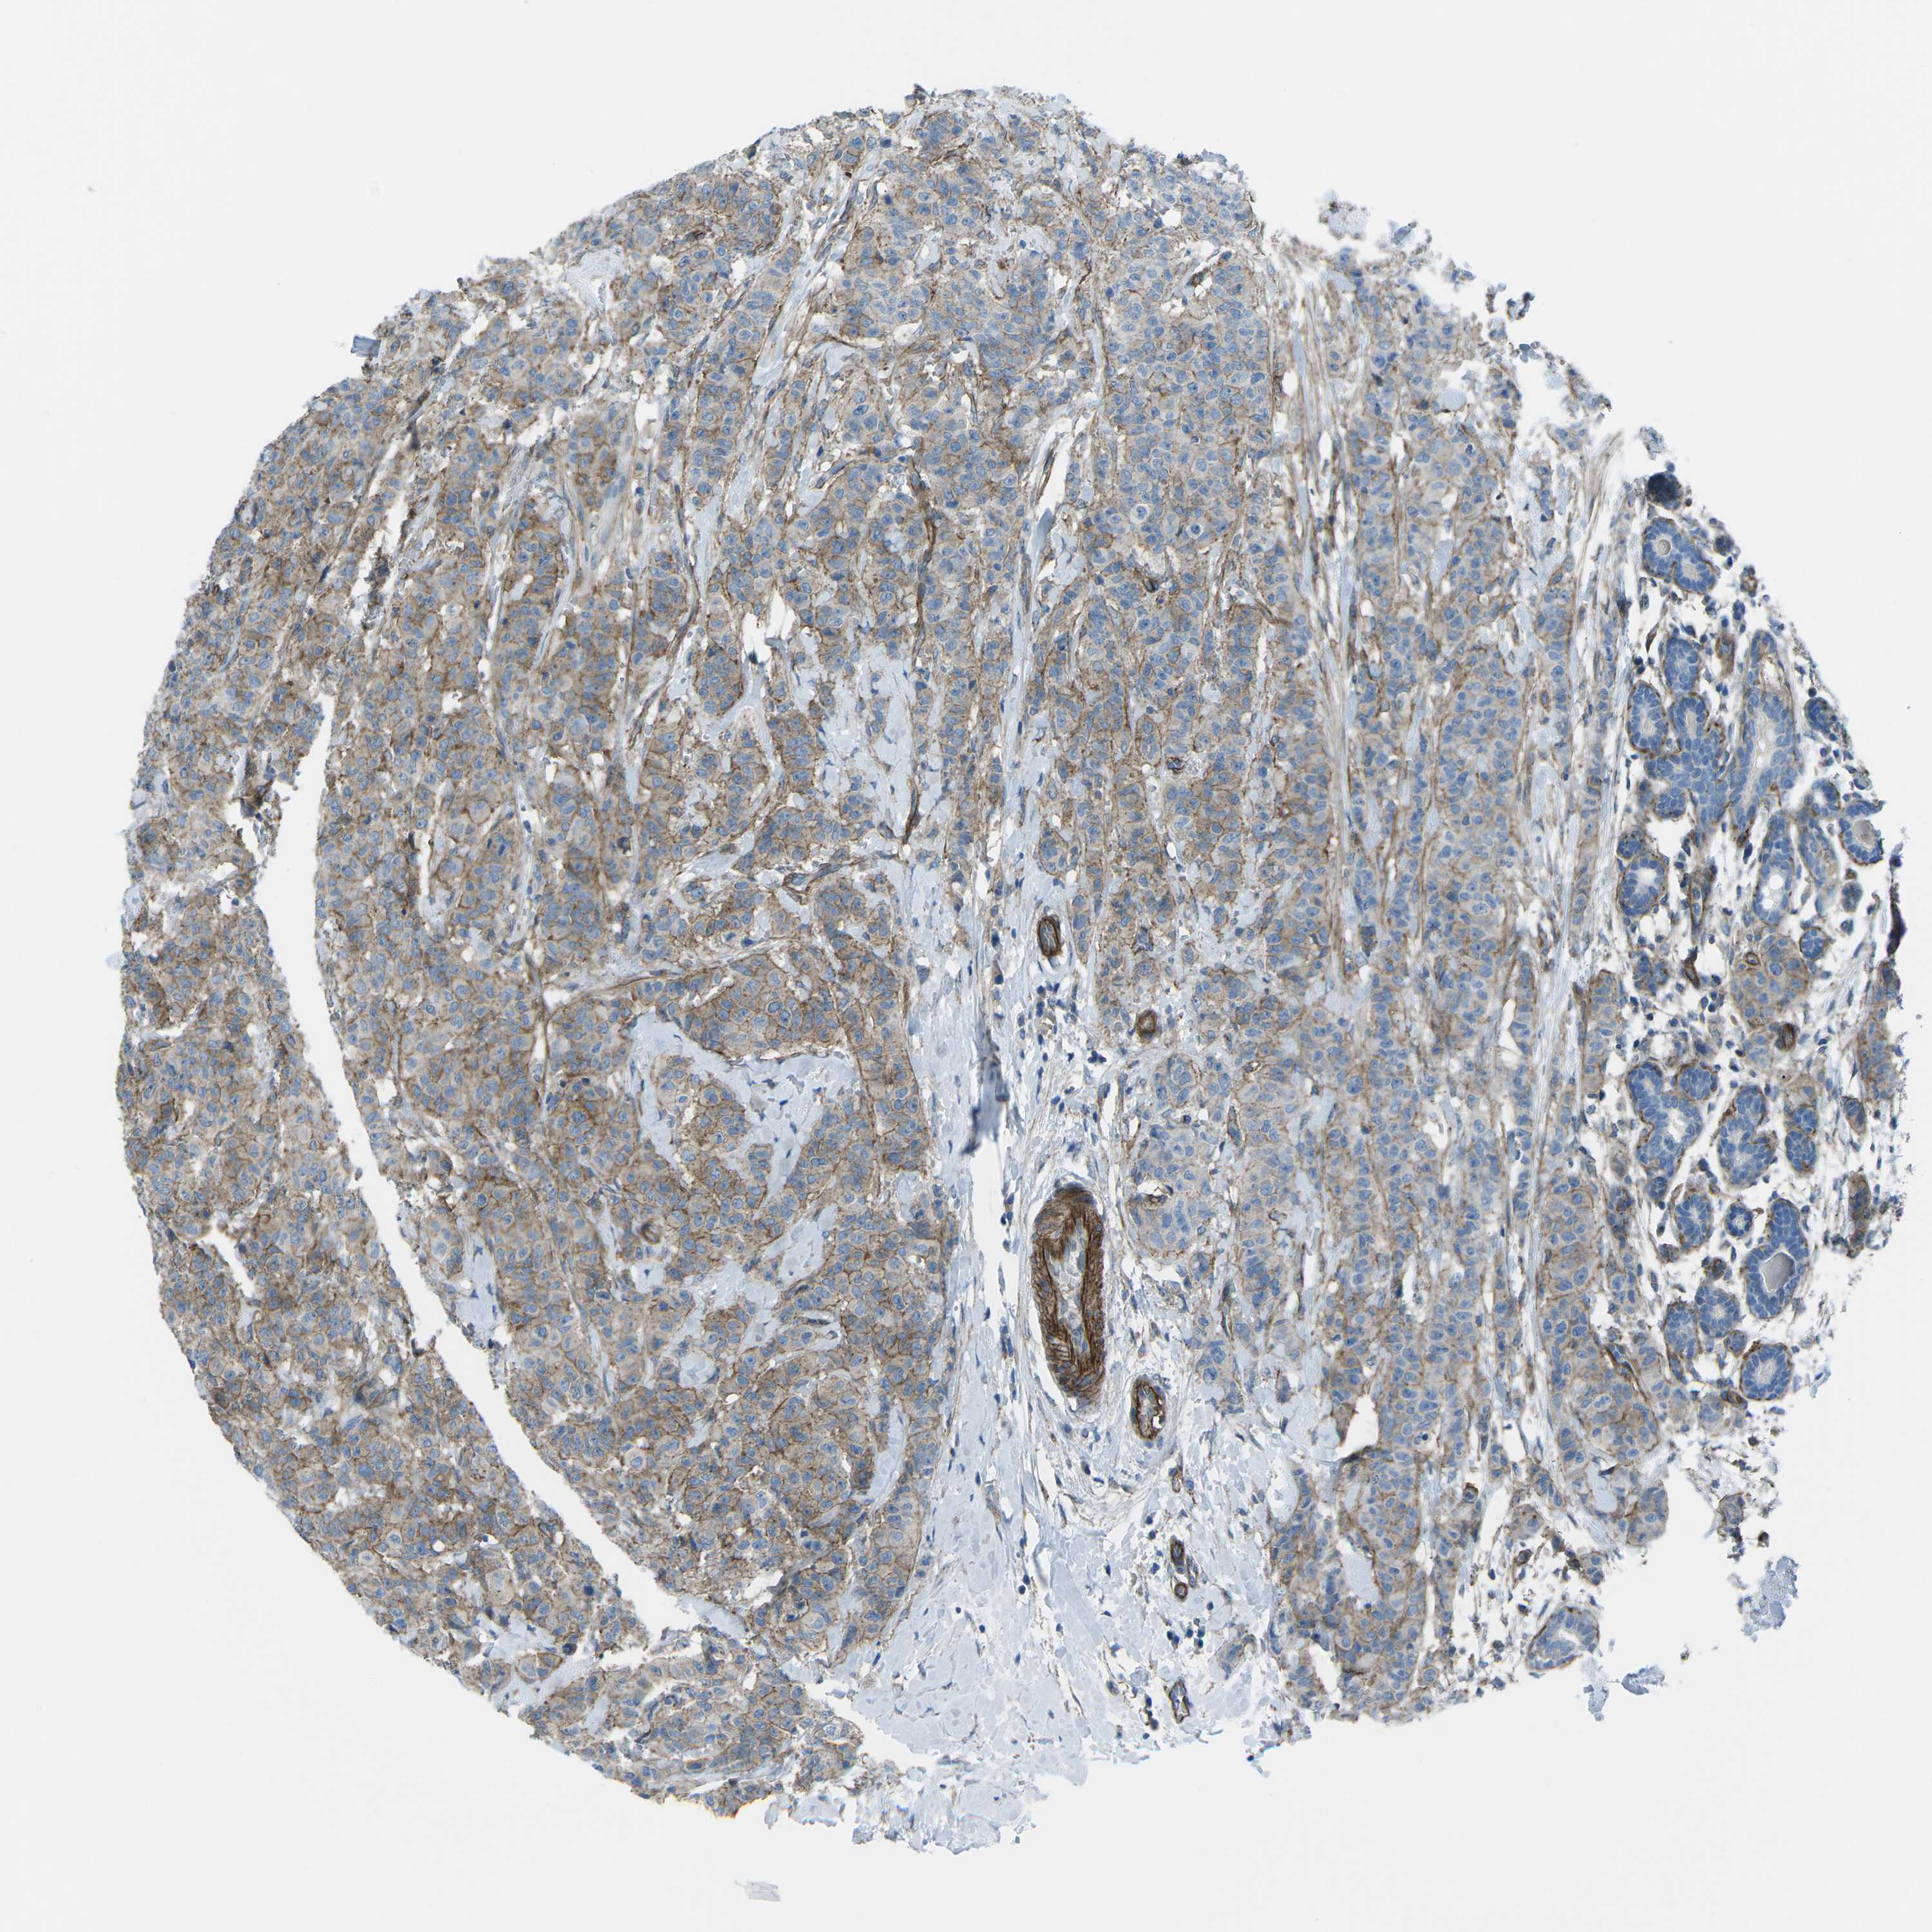

CANCER BREAST CANCER Show tissue menu

BRCA TCGA BRCA VALIDATION PROTEIN EXPRESSION